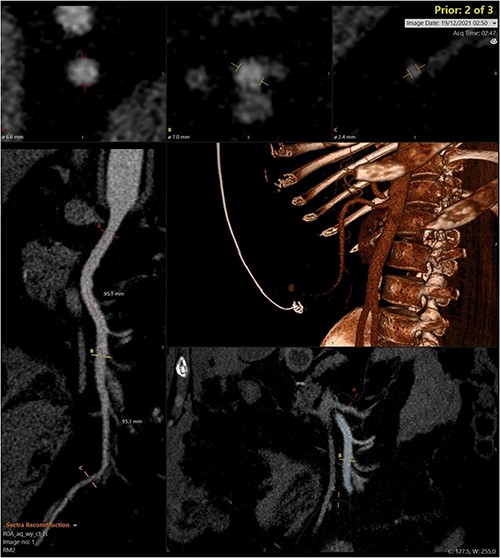

A CT abdomen-pelvis (CT-AP) revealed an acute haematoma inferolateral to the third part of the duodenum and another at the root of the mesentery. High density fluid related to the mesenteric bleed was also seen extending from the right para-colic gutter into the pelvis and in the peri-hepatic region. The patient was admitted under general surgery, stabilized with intra-venous fluid resuscitation, co-amoxiclav and metronidazole and cross matched for four units of blood. A CT-angiogram demonstrated acute haemorrhage throughout the abdomen with a 104 x 62 mm haematoma arising centrally at the level of L2 within the mesenteric fat (Fig. 1). The haematoma did not appear to originate from any specific mesenteric vessels but was related to some mid and distal jejunal loops. The angiogram also showed discontinuity when tracing the proximal and mid jejunal loops inferiorly, extensive haemorrhagic peritoneal fluid around the liver extending inferiorly (Fig. 2) and a small amount of peri-splenic haemorrhagic fluid. Curved reformatting of the angiogram revealed no abnormalities within the superior mesenteric artery (Fig. 3).

Curved reprogramming of the initial CT angiogram. Curved reprogramming of the patient’s initial CT angiogram showed no evidence of an aneurysm within the superior mesenteric artery, effectively ruling this out as a cause of the patient’s acute bleed.